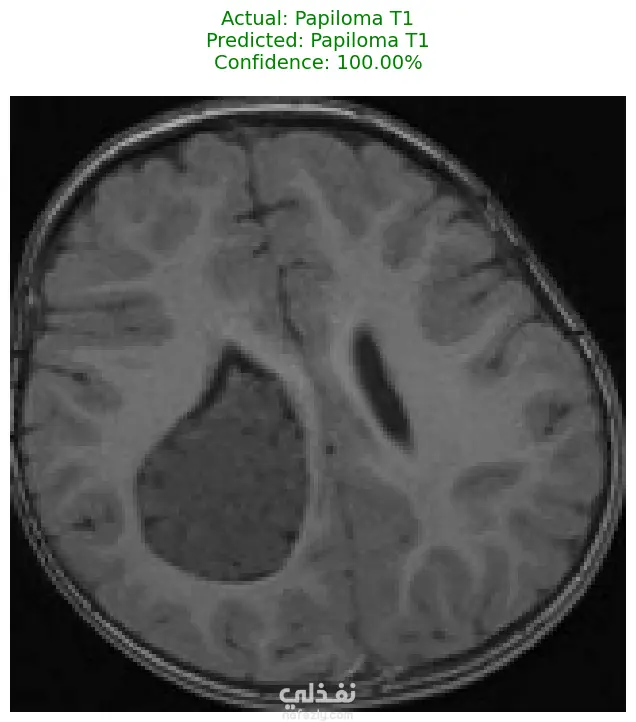

الوصف: قمت بتطوير نموذج تعلم عميق (CNN) قادر على التمييز بين 27 فئة مختلفة من الأورام والحالات الطبيعية بدقة تصل إلى 93%. شمل المشروع مراحل معالجة البيانات الضخمة، تنظيفها وموازنتها، وتصميم معمارية مخصصة لضمان الكفاءة العالية وتقليل استهلاك الذاكرة. المميزات التقنية: دقة استثنائية: حقق النموذج دقة تصل إلى 93% على بيانات التحقق (Validation Accuracy). معالجة البيانات الضخمة: تم العمل على قاعدة بيانات ضخمة، مع تطبيق استراتيجيات موازنة البيانات (Data Balancing) لضمان عدم انحياز الموديل. معمارية مخصصة: تم تصميم شبكة CNN تدعم تقنيات Batch Normalization لتسريع التعلم و Global Average Pooling لتقليل استهلاك الذاكرة وضمان استقرار النموذج. معالجة الصور: استخدام تقنيات OpenCV لقص الصور (Cropping) وإزالة الهوامش غير الضرورية لتركيز الموديل على منطقة الورم فقط. الأدوات والتقنيات المستخدمة: لغة البرمجة: Python. المكتبات الأساسية: TensorFlow / Keras. معالجة الصور: OpenCV & PIL. تحليل النتائج: Scikit-learn (Confusion Matrix & Classification Report). البيئة البرمجية: Google Colab (GPU Acceleration). النتائج المحققة: نموذج قادر على التعرف على أنواع نادرة من الأورام بدقة عالية. تقرير فني يوضح أداء الموديل لكل فئة (Precision & Recall). ملف نموذج جاهز للنشر (Deployment) بصيغة keras الحديثة. يمكنكم الاطلاع على الكود المصدري كاملاً والرسوم البيانية لتقييم أداء النموذج عبر رابط GitHub المرفق، كما يتوفر رابط تحميل النموذج المدرب داخل ملف الشرح.